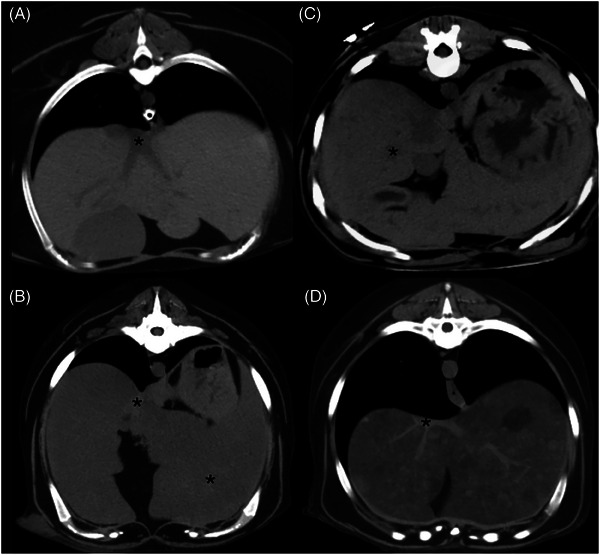

Hypoattenuation of the liver, consistent with hepatic steatosis or lipidosis, has been reported in veterinary patients. In people, measuring CT hepatic attenuation is diagnostic for hepatic steatosis, and hypoattenuation of the liver is defined as absolute if less than 40 HU or relative if the liver is 10 HU less than the spleen. The purpose of this study is to describe hepatic parenchymal attenuation in dogs with diabetes mellitus with or without diabetic ketosis (DK) or diabetic ketoacidosis (DKA), using the above categorization for absolute and relative hypoattenuation, as with humans. We hypothesized dogs with DK or DKA were more likely to have hypoattenuating livers. Twenty-seven diabetic dogs were included; fifteen were categorized in Group 1 as without DK or DKA, six in Group 2 as DK, and six in Group 3 as DKA. In Group 3, four of six dogs had absolute and relative hypoattenuating livers. Three of these were visually hypoattenuating to the vasculature, with one having negative attenuation and a histopathologic diagnosis of severe hepatic lipidosis. In Group 2, four of six dogs had relative hypoattenuating livers. In Group 1, only one of 15 dogs had a relatively hypoattenuating liver. Groups 2 and 3 had significantly lower absolute liver attenuation than Group 1. Presumed hepatic steatosis was present on CT and was more common with DK or DKA. These findings may help provide hepatic sampling recommendations and alter patient prognosis. Further research is needed to establish absolute and relative liver attenuation in dogs with correlation to histopathology and patient outcome.